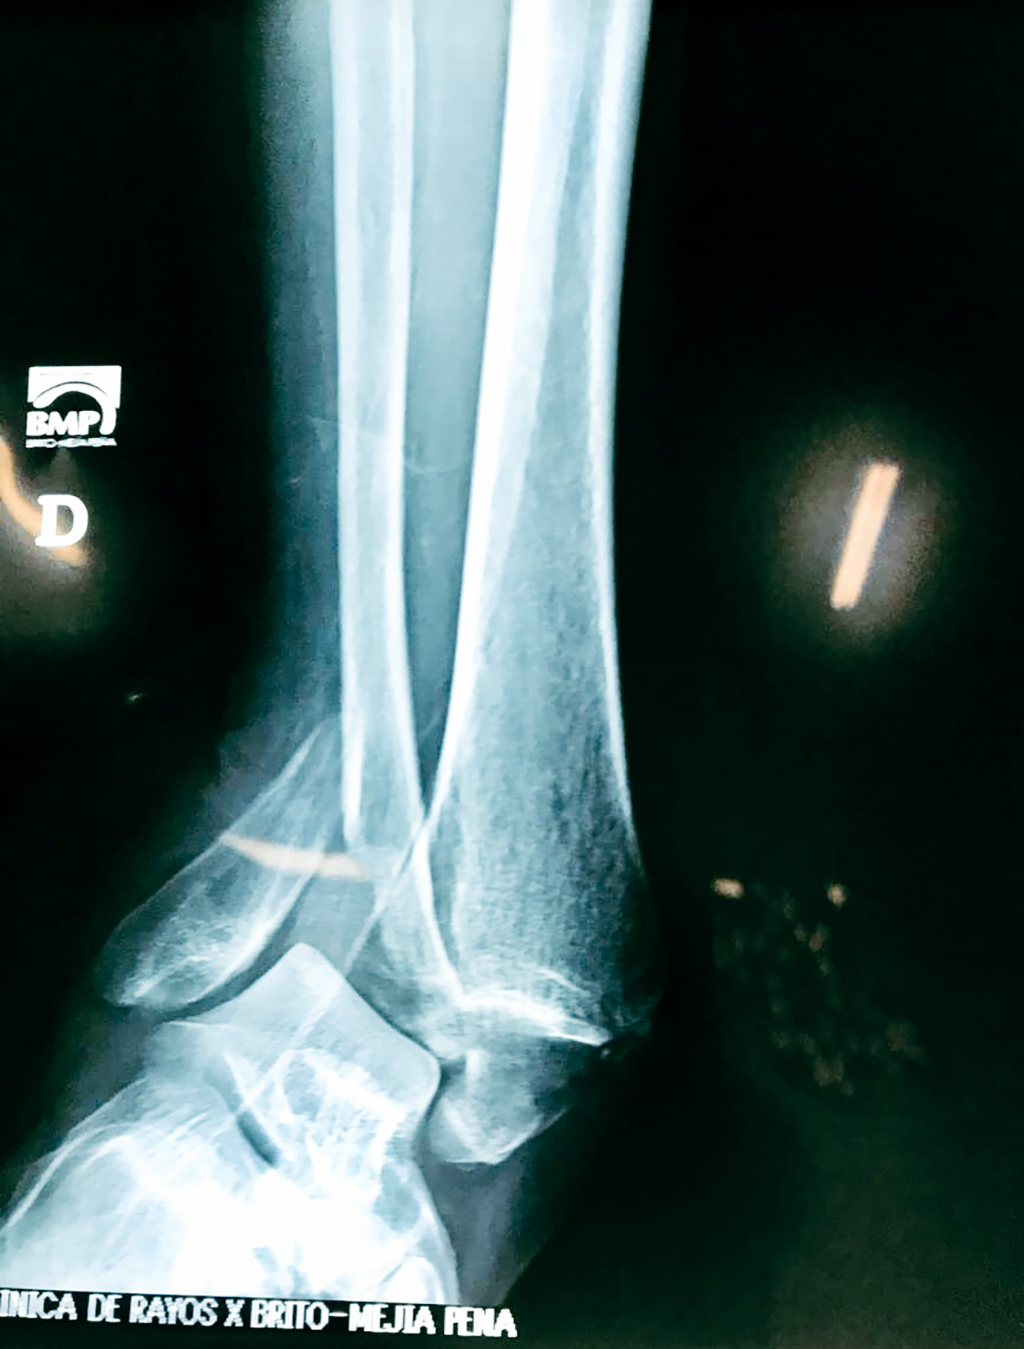

Una fractura de tobillo es la rotura de uno o más de los huesos del tobillo. Estas fracturas pueden ser:

- Completas (el hueso está perforado y está en 2 partes).

- Los extremos de los huesos están desalineados entre sí (desplazados).

- La fractura se extiende hasta la articulación del tobillo (fractura intra-articular).

- Los tendones o ligamentos (tejidos que sujetan los músculos y los huesos entre sí) están rotos.